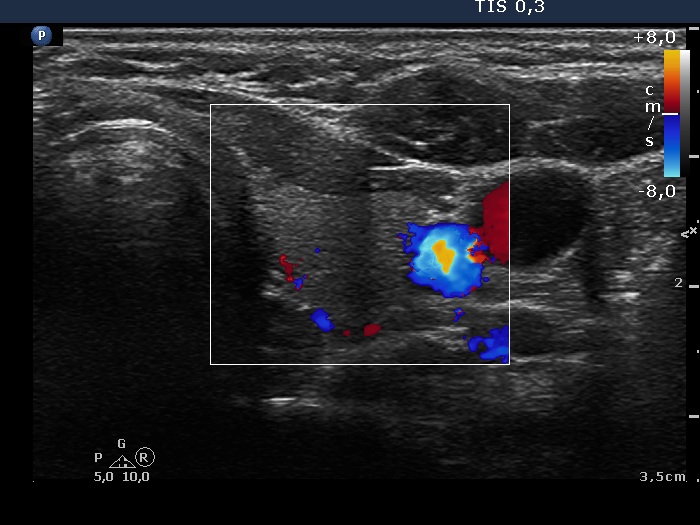

Intranodular hyperechogenic figures - case 1726 (ultrasonographic picture 6)

Left lobe, transverse scan, color Doppler mode.